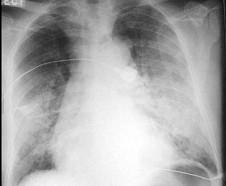

问题 男,70岁,高血压病史20年,突然出现心悸、气促,咳粉红色泡沫痰,血压210/130mmHg,心率138次/分,律不齐,行床旁胸片检查,结果如图所示,应该选择以下哪项治疗 ( )

选项 A、硝普钠、多巴胺、酚妥拉明 B、硝酸甘油、西地兰、多巴胺 C、美托洛尔、速尿、肾上腺素 D、毒毛旋花子苷K、普萘洛尔(心得安)、哌唑嗪 E、硝普钠、西地兰、速尿

答案 E